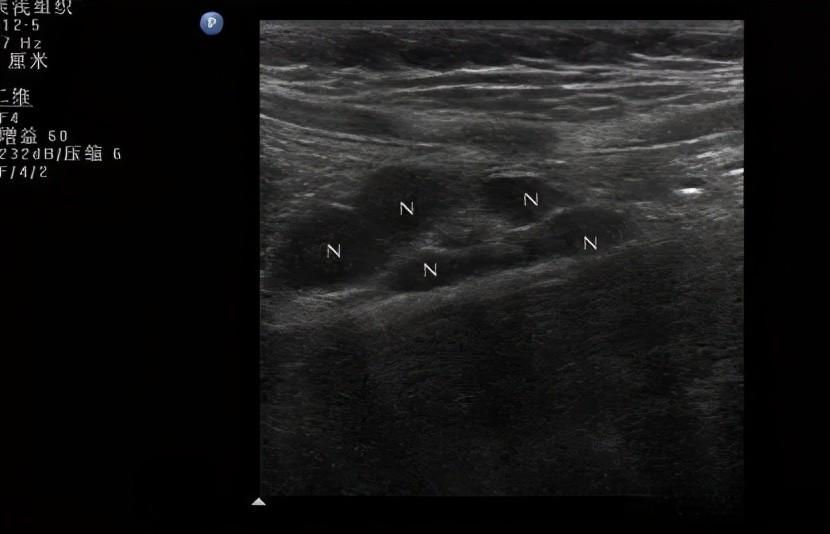

肠系膜淋巴结肿大是指腹部B超检查发现肠系膜区域的淋巴结增大。这种状况在儿科门诊中发生率极高,特别是在15岁以下儿童中较为常见。患者通常会出现腹痛、恶心、呕吐等症状,腹痛多位于脐周或接近脐周。

在诊断方面,目前尚无统一的诊断标准。国内多数学者认为,在一个切面内肠系膜区域显示3个以上淋巴结,最大淋巴结长径>1.0 cm,短径>0.5 cm,长径/短径>2可以诊断为肠系膜淋巴结肿大。而国外多数学者以最大淋巴结长径>2.0 cm,最大淋巴结短径>1.0 cm作为标准,显著高于国内标准,可能与人种差别有关。